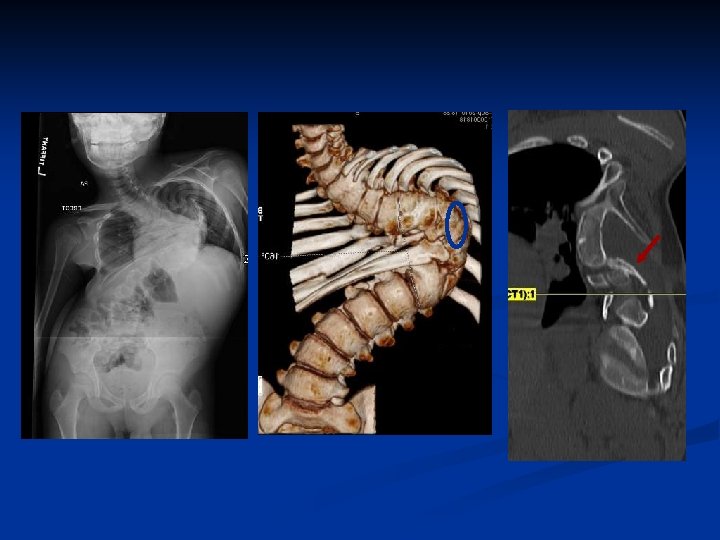

Patient GF n 12 yo boy with congenital scoliosis, diastematomyelia n Laminectomy and partial resection of diastematomyelia at age 4 n Progressive, severe scoliosis and increased pain with ambulation

Options n Considered resection of diastematomyelia; however… n Shen et al SRS 2010 n 95 patients with diastematomyelia underwent deformity surgery n None prophylactically removed n No neurological

Post-op X-rays